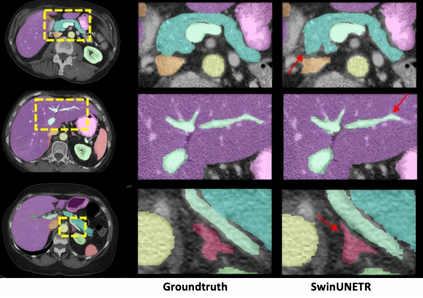

Transformer, the latest technological advance of deep learning, has gained prevalence in natural language processing or computer vision. Since medical imaging bear some resemblance to computer vision, it is natural to inquire about the status quo of Transformers in medical imaging and ask the question: can the Transformer models transform medical imaging? In this paper, we attempt to make a response to the inquiry. After a brief introduction of the fundamentals of Transformers, especially in comparison with convolutional neural networks (CNNs), and highlighting key defining properties that characterize the Transformers, we offer a comprehensive review of the state-of-the-art Transformer-based approaches for medical imaging and exhibit current research progresses made in the areas of medical image segmentation, recognition, detection, registration, reconstruction, enhancement, etc. In particular, what distinguishes our review lies in its organization based on the Transformer's key defining properties, which are mostly derived from comparing the Transformer and CNN, and its type of architecture, which specifies the manner in which the Transformer and CNN are combined, all helping the readers to best understand the rationale behind the reviewed approaches. We conclude with discussions of future perspectives.